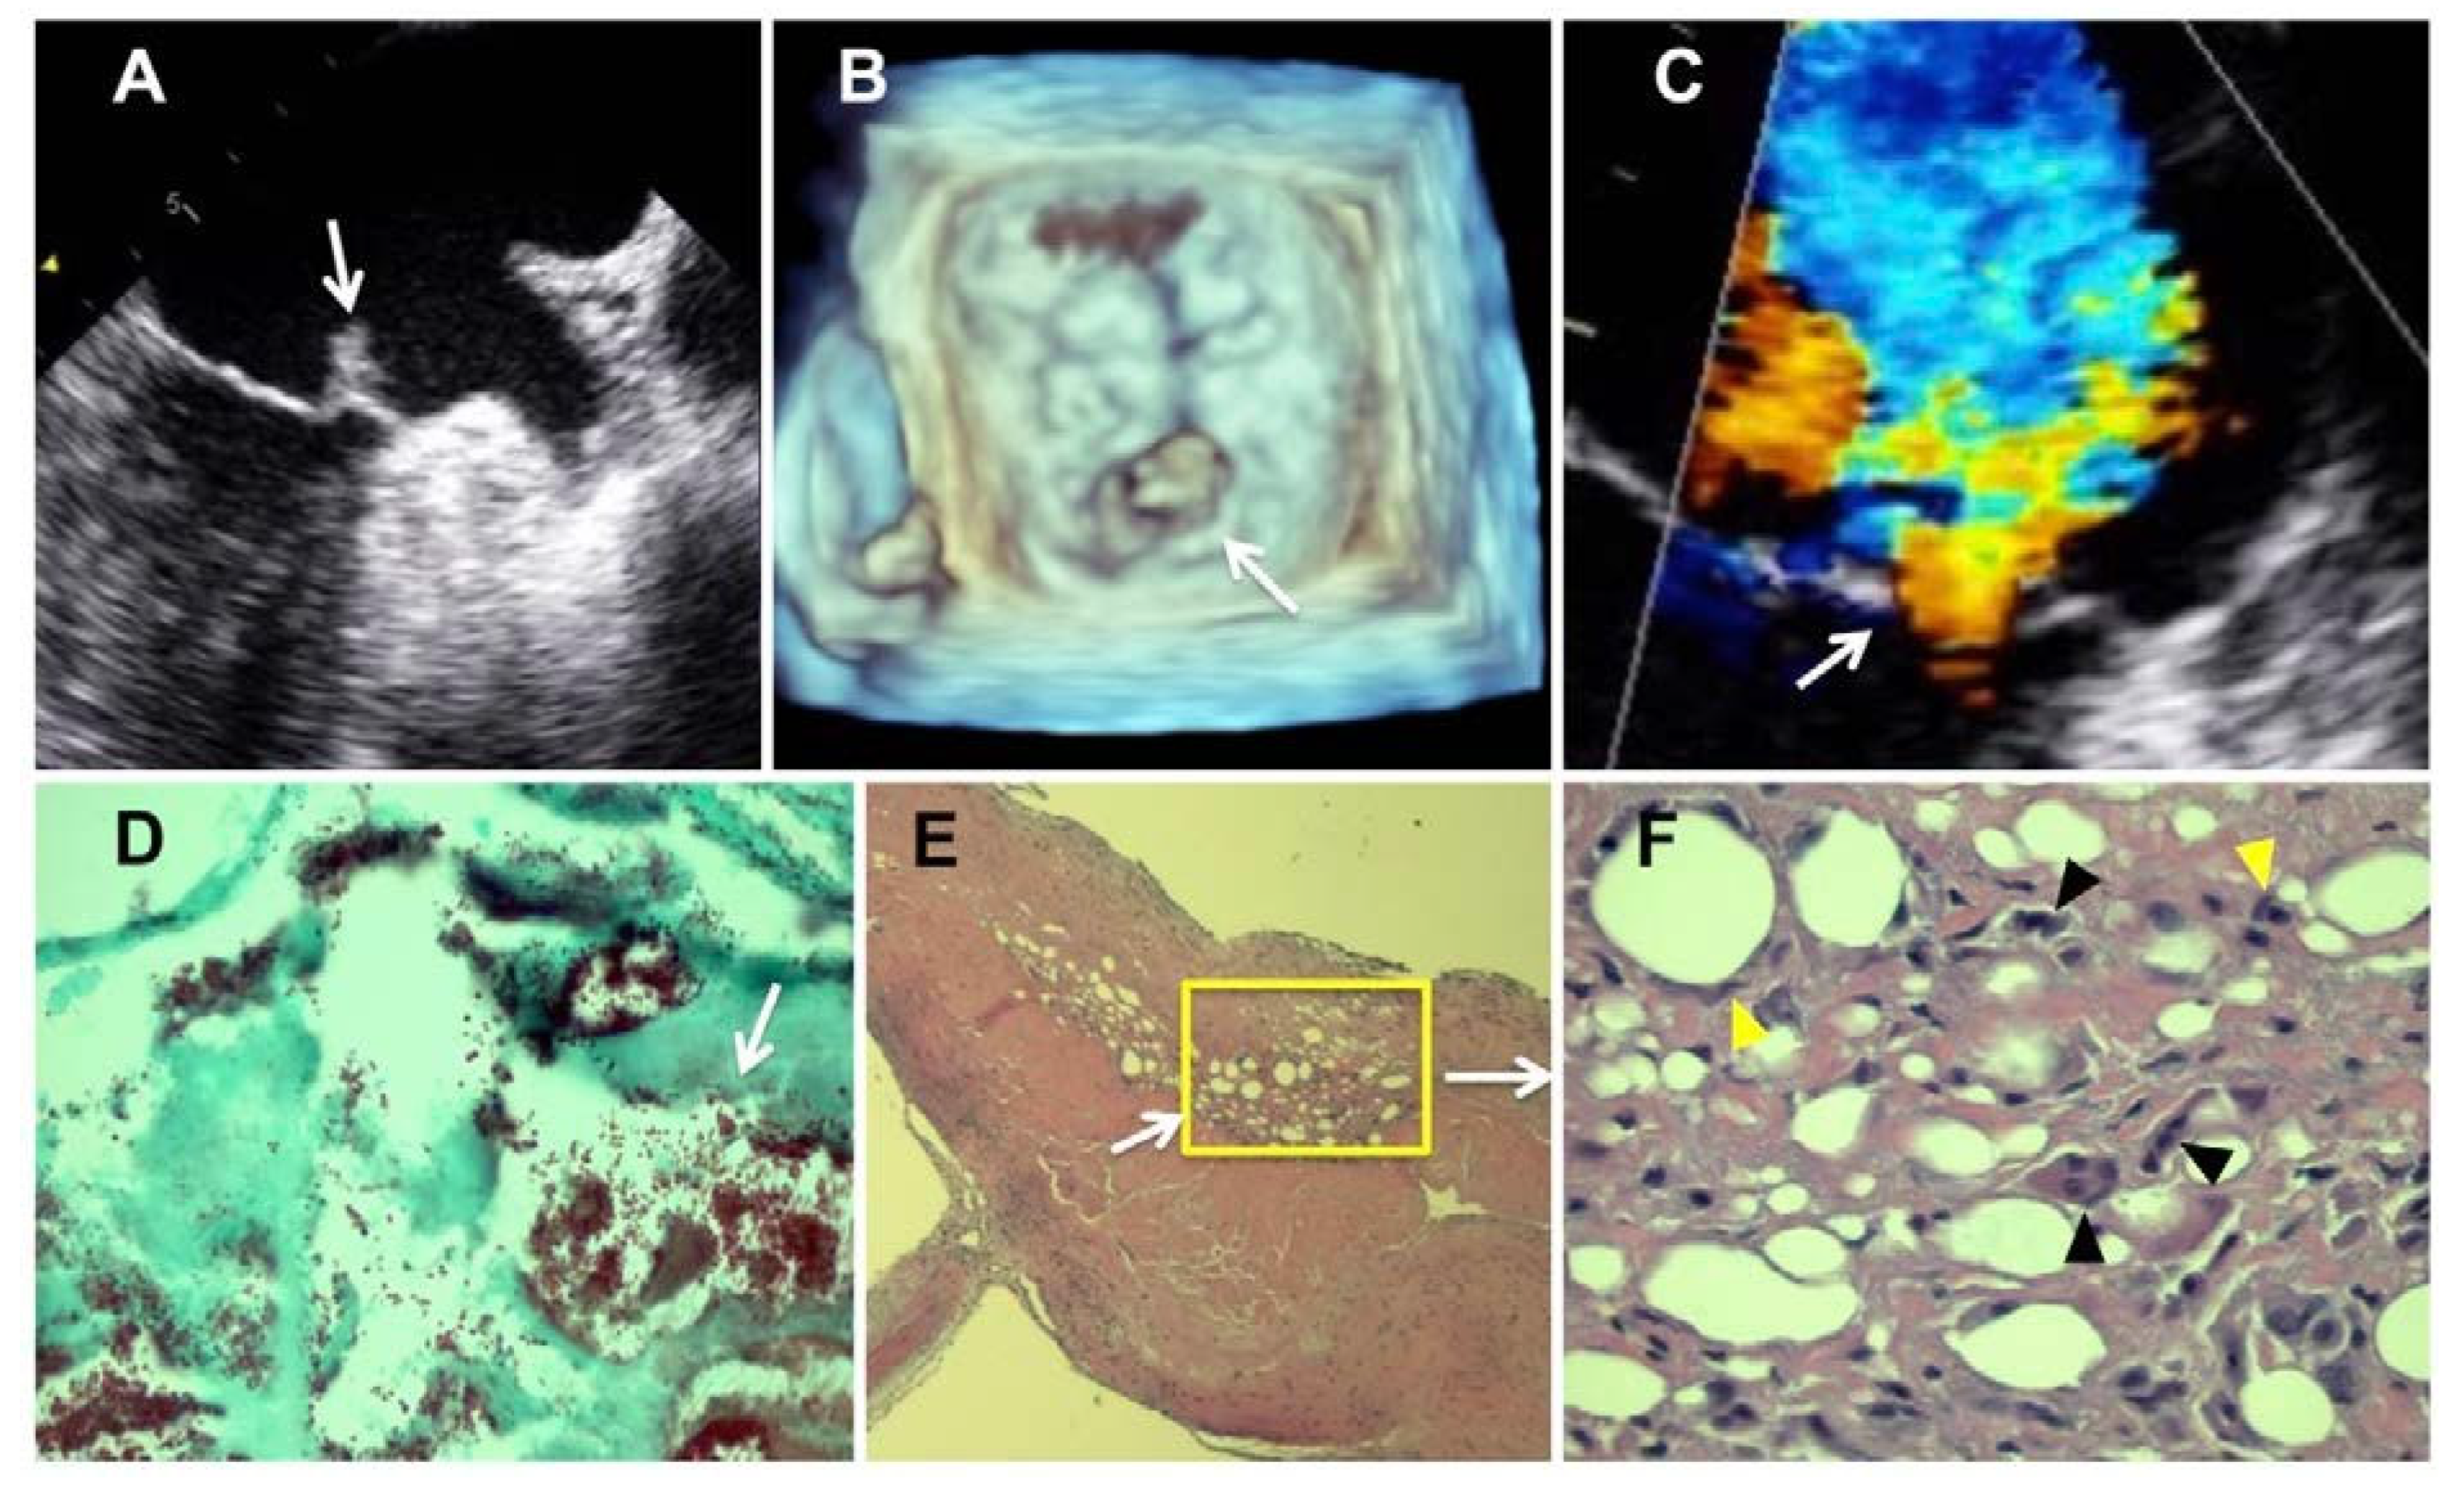

Case report

Pathology results